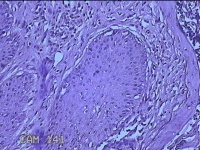

性别

男

年龄

45岁

临床诊断

皮下结节

一般病史

发现左侧一结节,伴局部瘙痒不适1年。

标本名称

左侧结节

大体所见

灰白暗红色带皮肤样结节0.8x0.7x0.3cm一个,表面糜烂,切开结节呈实性,切面灰白粉红色,质软。

图1

感觉像表皮样囊肿?